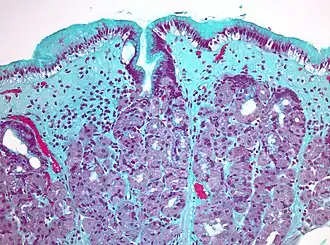

Коллагеновый гастрит, окраска трихромом Массона